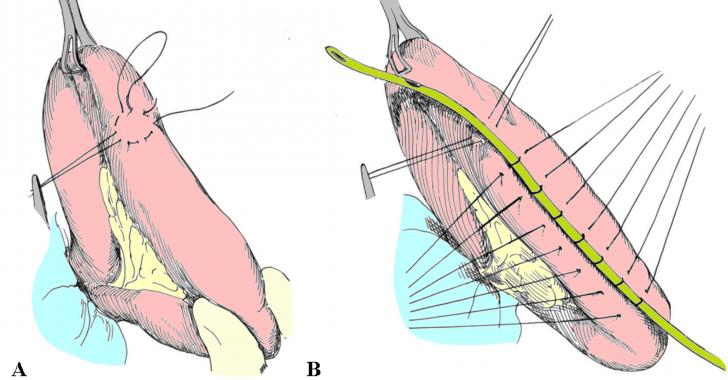

JEJUNOSTOMIA - CHIRURGIE

JEJUNOSTOMIA - CHIRURGIE I. DEFINITIE Jejunostomia este actul chirurgical prin care se stabileste o comunicare intre lumenul unei anse jejunale si exterior, cu scopul introducerii alimentelor/preparatelor de nutritie enterala sau evacuarii cCiteste tot ... 2346 cuvinte

Dimensiune medie

+ cu poze |